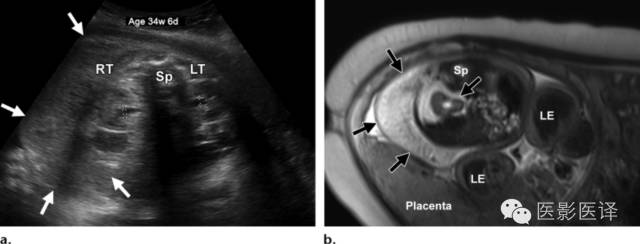

图19.孕34周6天胎儿淋巴管瘤。超声横断面(a)和T2加权MR横断面(b)显示腹膜后较大肿块(箭),包绕右肾。肿块位于腹膜后,鉴别诊断中可以排除卵巢肿物。LE=下肢,LT=左肾,Sp=脊柱